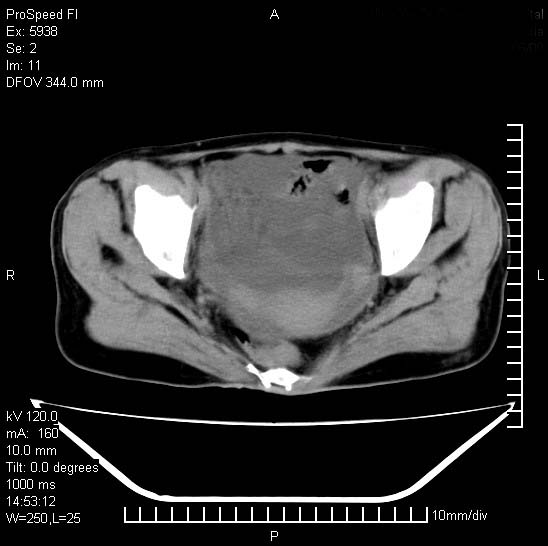

反复小腹疼痛,盆腔积液3年,无发热,曾抗痨一段时间。

右下腹肠管壁增厚,边缘有侵润改变及点状低密度影,内侧可见局限性肿块。考虑-----淋巴瘤或增生型肠结核----盆腔积液-----建议肠镜检查

考虑盆腔及右下腹感染性病变(结核可能)。

结核性腹膜炎伴积液。右侧髂骨骨窗看看,是否有骨质破坏。

提示结核性腹膜炎合并盆腔积液。建议查ppd或tb抗体。